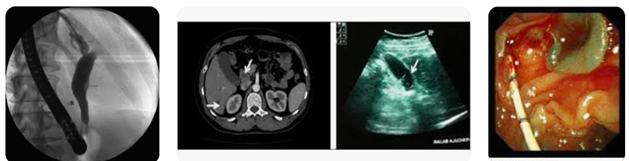

Hình 7. Áp dụng thủ thuật ERCP trong chẩn đoán và lấy sán ra đường mật tụy

Hình 8. Áp dụng thủ thuật ERCP trong chẩn đoán và lấy sán ra đường mật tụy

Hình 9. Phối hợp Siêu âm, CT-scan và thủ thuật ERCP trong điều trị sán lá gan lớn ở mật-tụy

Trong pha đường mật, CT scanner cho thấy hình ảnh dãn ống dẫn mật ở vị trí trung tâm sán nằm và có sự giảm âm ở vùng ngoại vi (vết) và siêu âm có giá trị xác định con sán di động khi chúng còn di chuyển trong hệ đường mật.

Thủ thuật nội soi mật tụy ngược dòng (Endoscopic Retrograde Cholangio-pancreatography) vừa có giá trị thăm dò, phát hiện, chẩn đoán, vừa có giá trị điều trị giải quyết trực tiếp sán Fasciolasp. kẹt trong hệ thống đường mật, nhất là trong pha/ giai đoạn sán lá nằm ở hệ đường mật thì thủ thuật này giúp lấy sán và cầm máu nếu có dấu xuất huyết đi kèm.